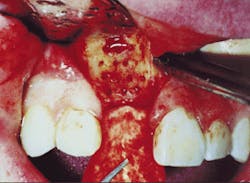

The graft material should completely fill the socket to the height of the alveolar crest (Figure 1). The placement of the graft material is accomplished in approximately 5 mm increments to ensure a uniform density throughout the graft. Upon placement, each of these layers is condensed into the socket firmly, but loose enough to maintain the blood supply throughout the graft. The close approximation of the grafting material to the fresh, clean bony wall optimizes the osteogenic potential of the site.

Figure 1